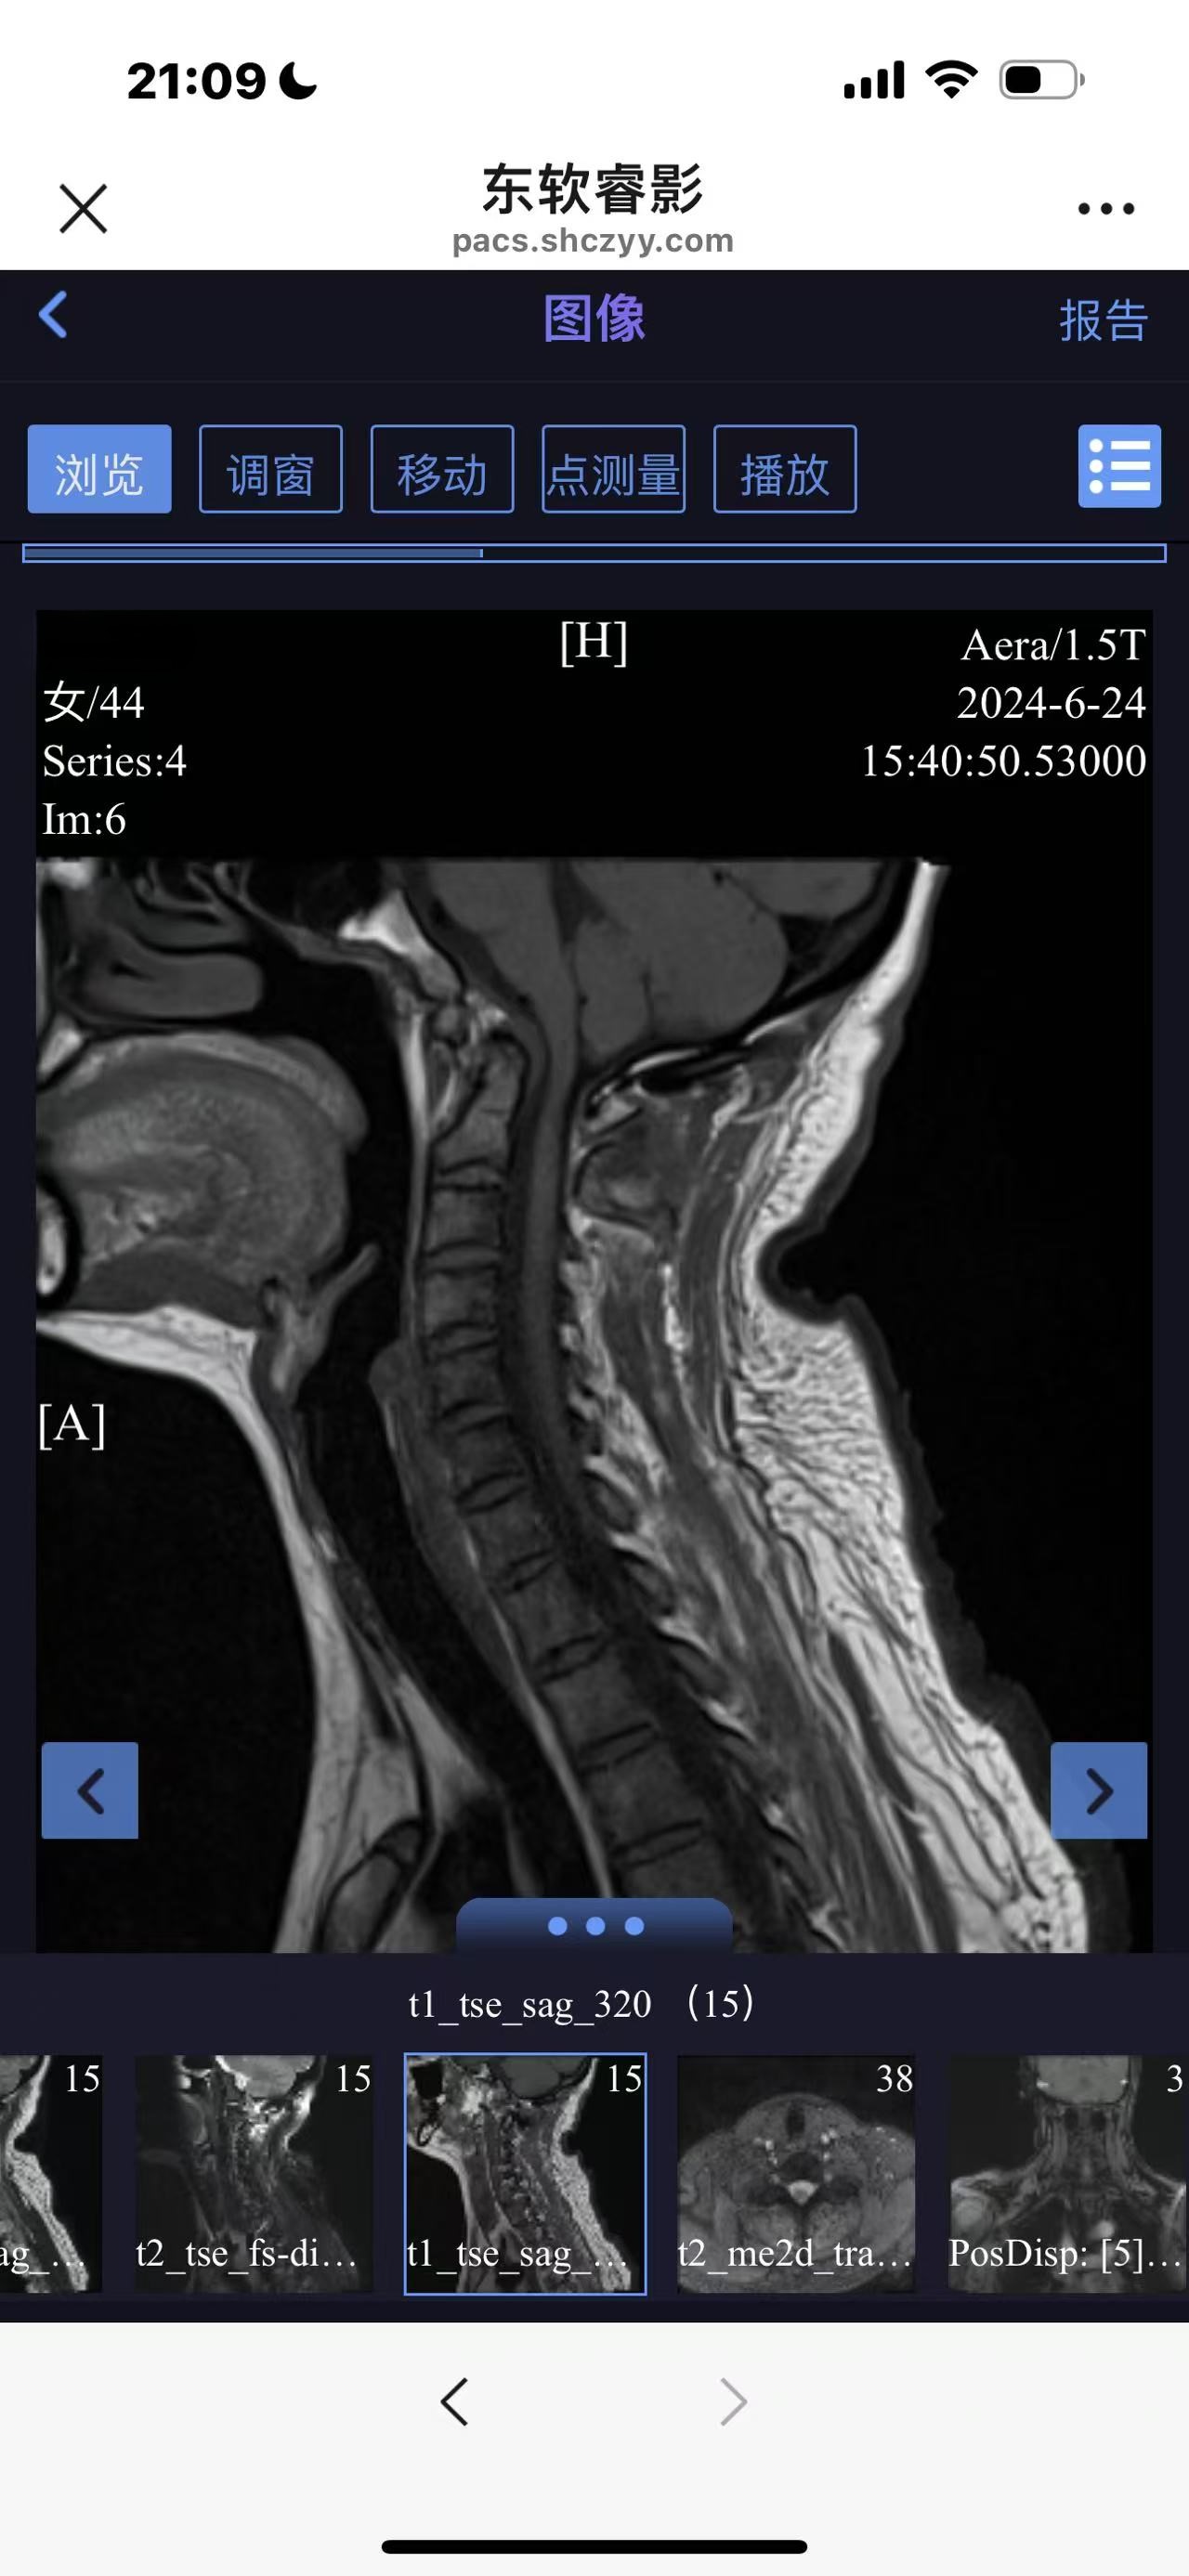

• 诊断:寰枢椎脱位

• 影像:

• 日期:2024.06

• 医院:上海长征医院

• 术后状况:没有复位

• 术后影像: